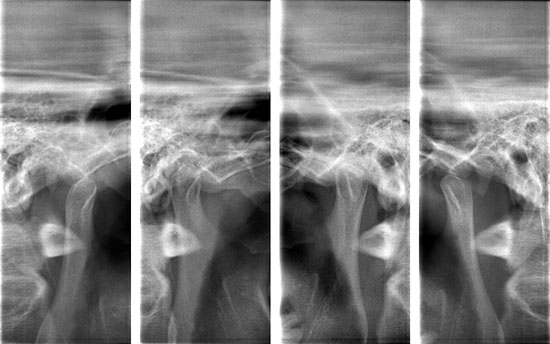

| Ⅳ 型 | 下顎の骨の上部が削り取られたり、出っ張ったりし(下顎頭の変形)、口を開閉すると 「ギリギリ」と音 がしたり、 炎症による痛み が生じたりします。 | 当院では、顎の関節を撮影できるレントゲンがございます。このレントゲンにより画像診断を行って、重度の外科処置が必要な場合には、大学病院へ紹介することができます。![]() |